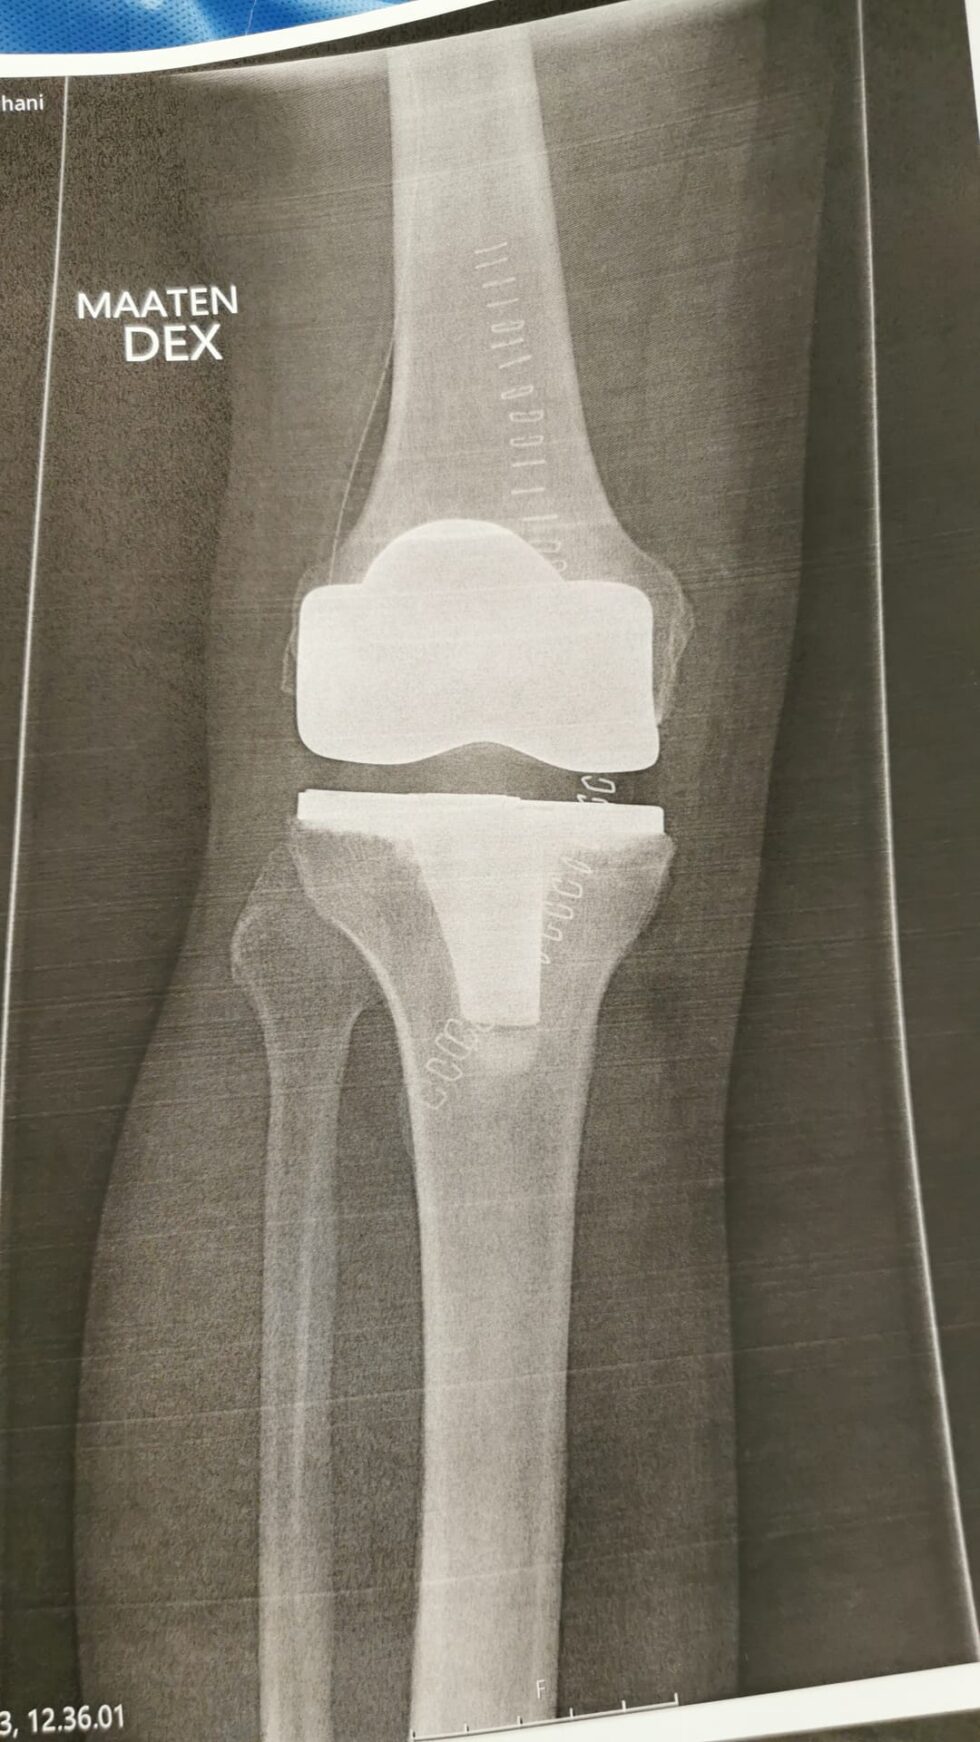

Arto Kojon tekonivelpäiväkirja

• Arto Kojon tekonivelpäiväkirja